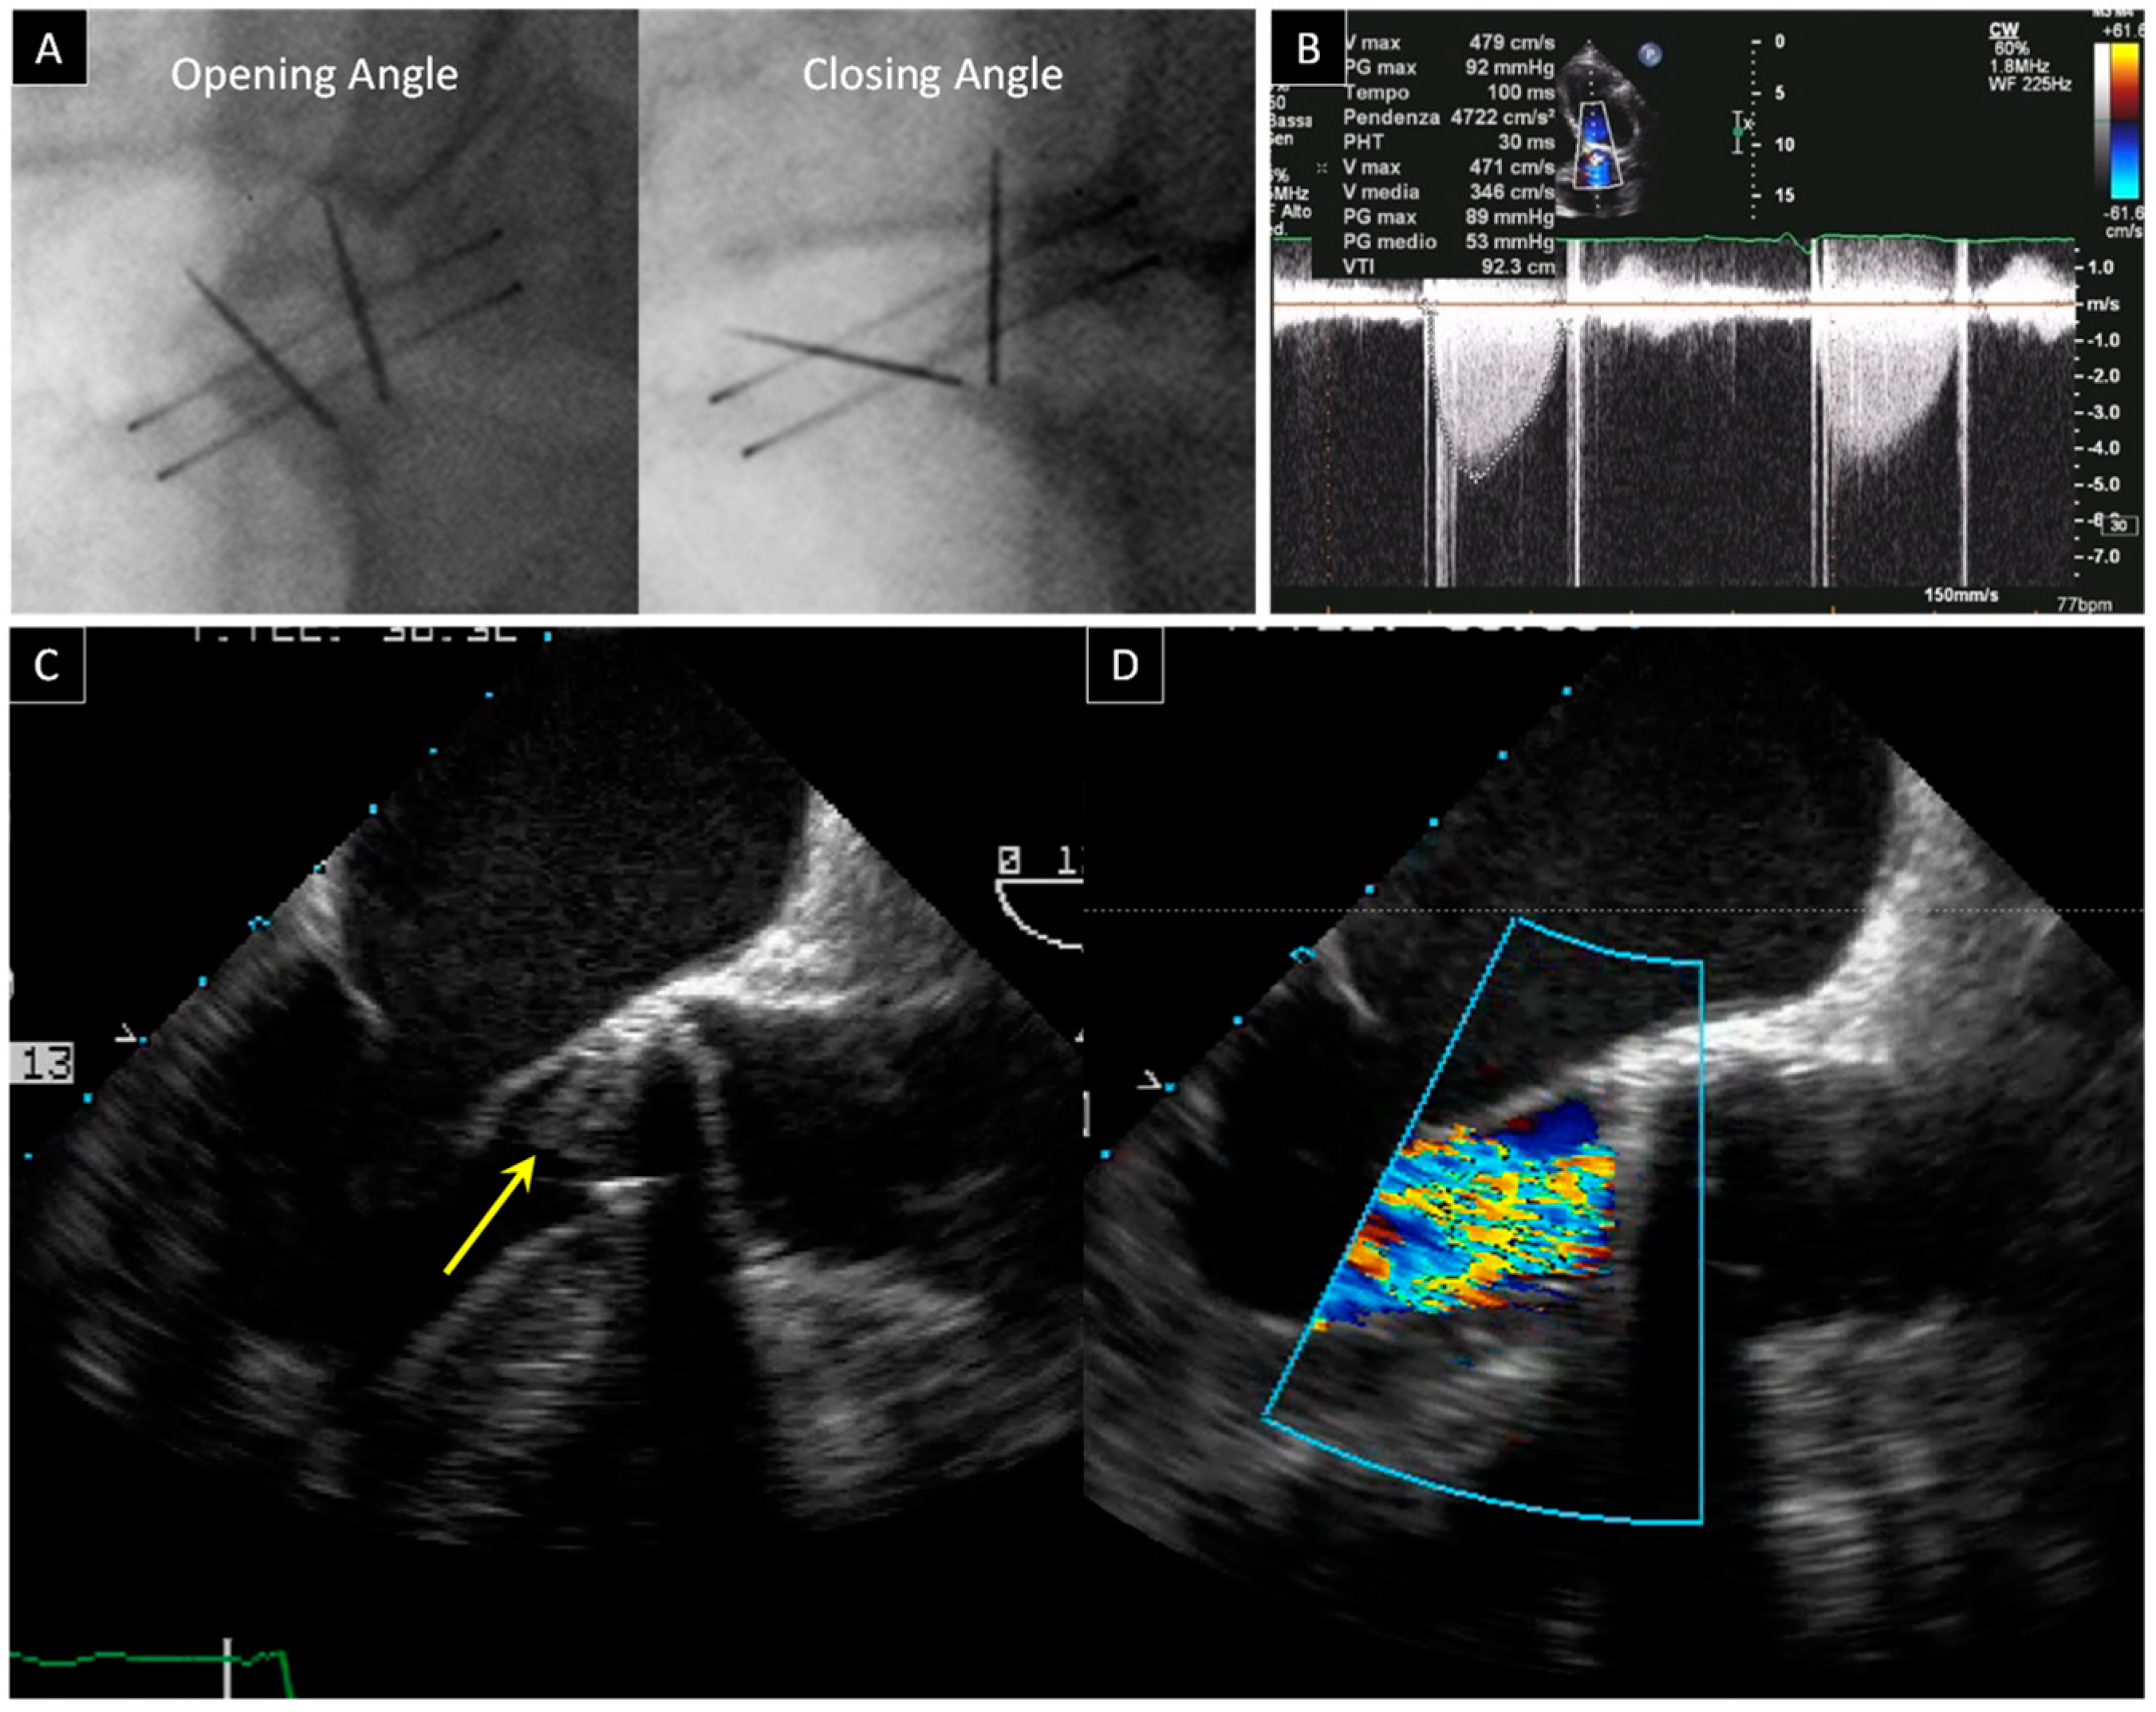

2.2. Prosthetic Aortic Valve Obstruction